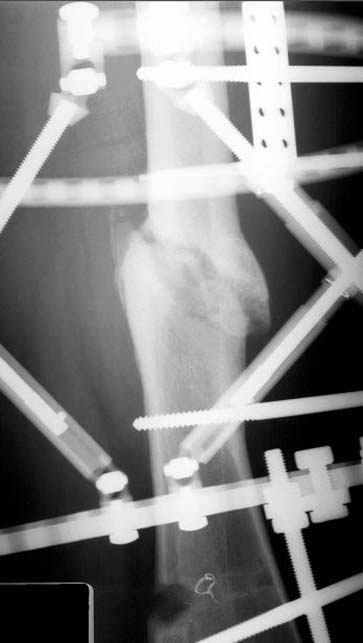

Если, например, доводится лечить больных с псевдартрозами шейки бедра, то надобность есть, и приходится. См. приложение.

На рисунке N1 предоперационный план лечения ложного сустава шейки бедра- линия ложного сустава, угол и направление введения импланта, клиновидная остеотомия в градусах и миллиметрах, второй снимок после коррекции, расчет, на сколько удлиняется конечность и размеры импланта;

N3 рисунок окончательный снимок, после операции моя рентгенограмма должен выглядеть примерно как эта картина. На N4 снимке клин перед удалением; N5 послеоперации 3 нед.; N6 окончательная рентгенограмма.

(доложен в Ст. Петербурге 2003 и в Москве 2004)

варус при проксимальном отделе 95 градусной пластиной.